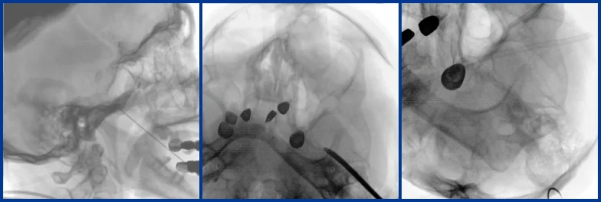

Integrated C-Arm with a Large FPD Assists Pain Management Department in Performing Spinal Cord Stimulation Implantation

Mobile Flat-Panel C-Arm Supports Trigeminal Ganglion Balloon Compression Surgery

Perlove Medical’s mobile flat-panel interventional C-arm meets the needs of most interventional procedures. For complex pain treatments, such as vascular interventions and tumor-related pain management, its real-time dynamic imaging and wide field of view offer comprehensive intraoperative imaging support throughout the entire procedure.